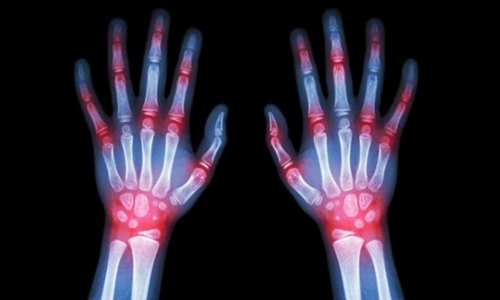

2、关节肿痛。

尿酸过高就会在血液中形成结晶,并且沉积在血液中,而血液中的结晶会向身体的各个关节运输,关节肿大诱发关节炎 ,自然就能关节肿痛了。